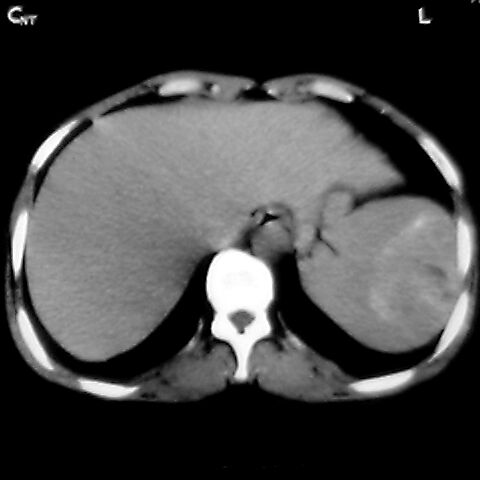

女 48岁 食道癌术前体检发现脾占位。

脾胀内部巨大低密度肿块,边界清或不清,中心坏死,轻度增强,内见散在钙化,结合食道癌病史多考虑:转移癌.

考虑脾脏血管瘤,中央低密度为血栓形成

脾脏低密度灶伴钙化,增强化明显,中心见液化坏死灶,强化延时明显。考虑血管瘤。转移瘤待排。